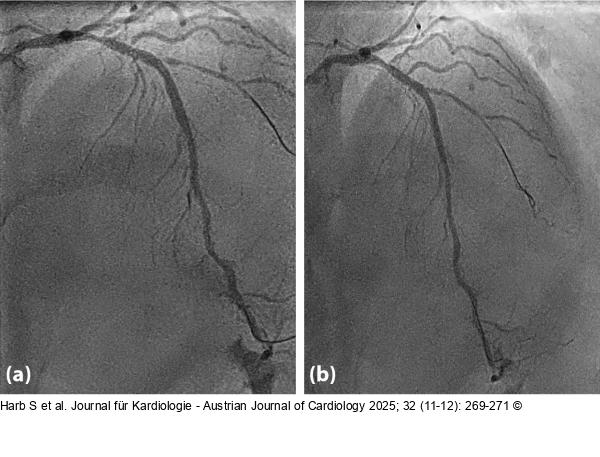

Abbildung 4: Result (a) Result after scoring balloon and (b) after drug-eluting balloon |

Abbildung 4: Result

(a) Result after scoring balloon and (b) after drug-eluting balloon |